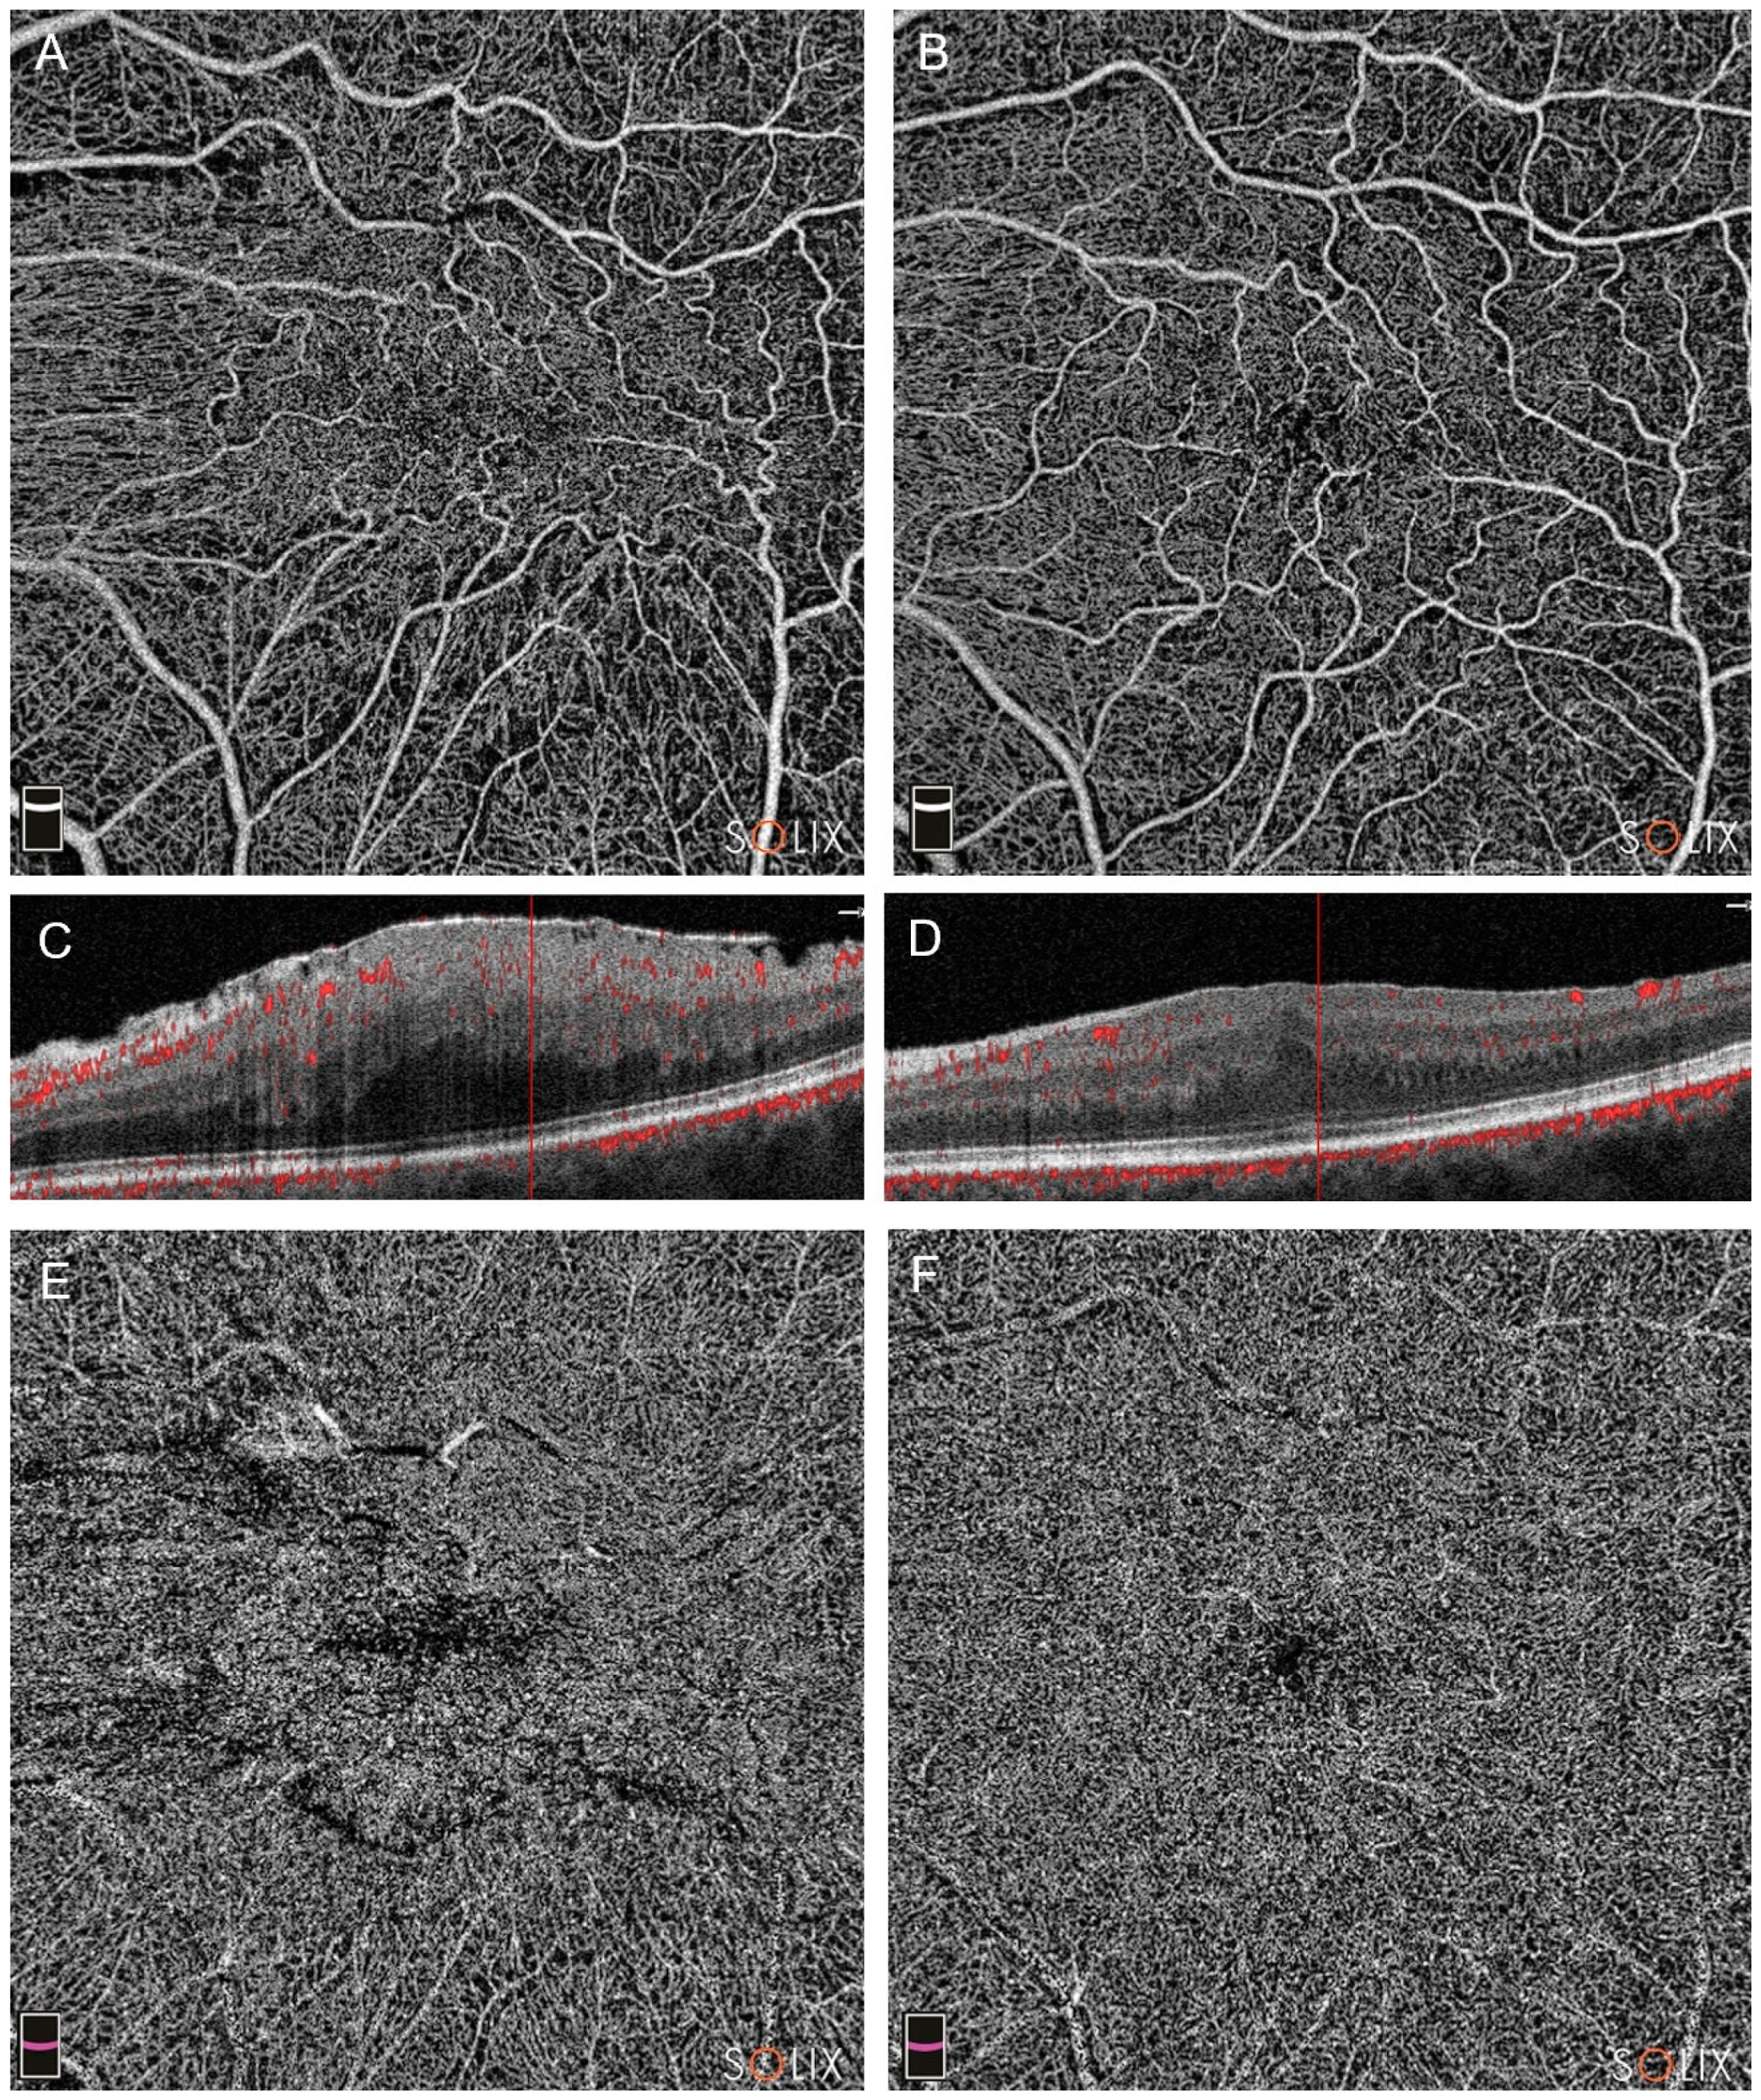

3.1. OCTA Findings